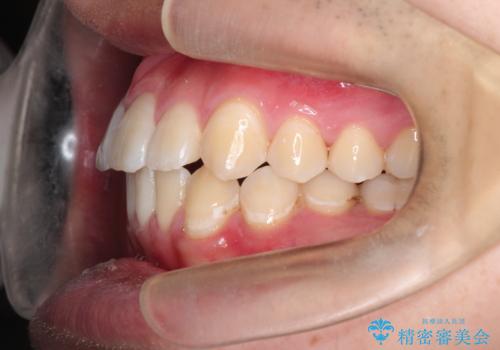

【ワイヤー矯正】前歯の凸凹を治したい。

- 前歯の凸凹を主訴に来院されました。

患者様がマウスピース矯正の使用時間に不安があるため、ワイヤー矯正にて治療を行なっております。

ワイヤー矯正は使用時間の制約がないため、マウスピースの装着管理が苦手な人には向いています。